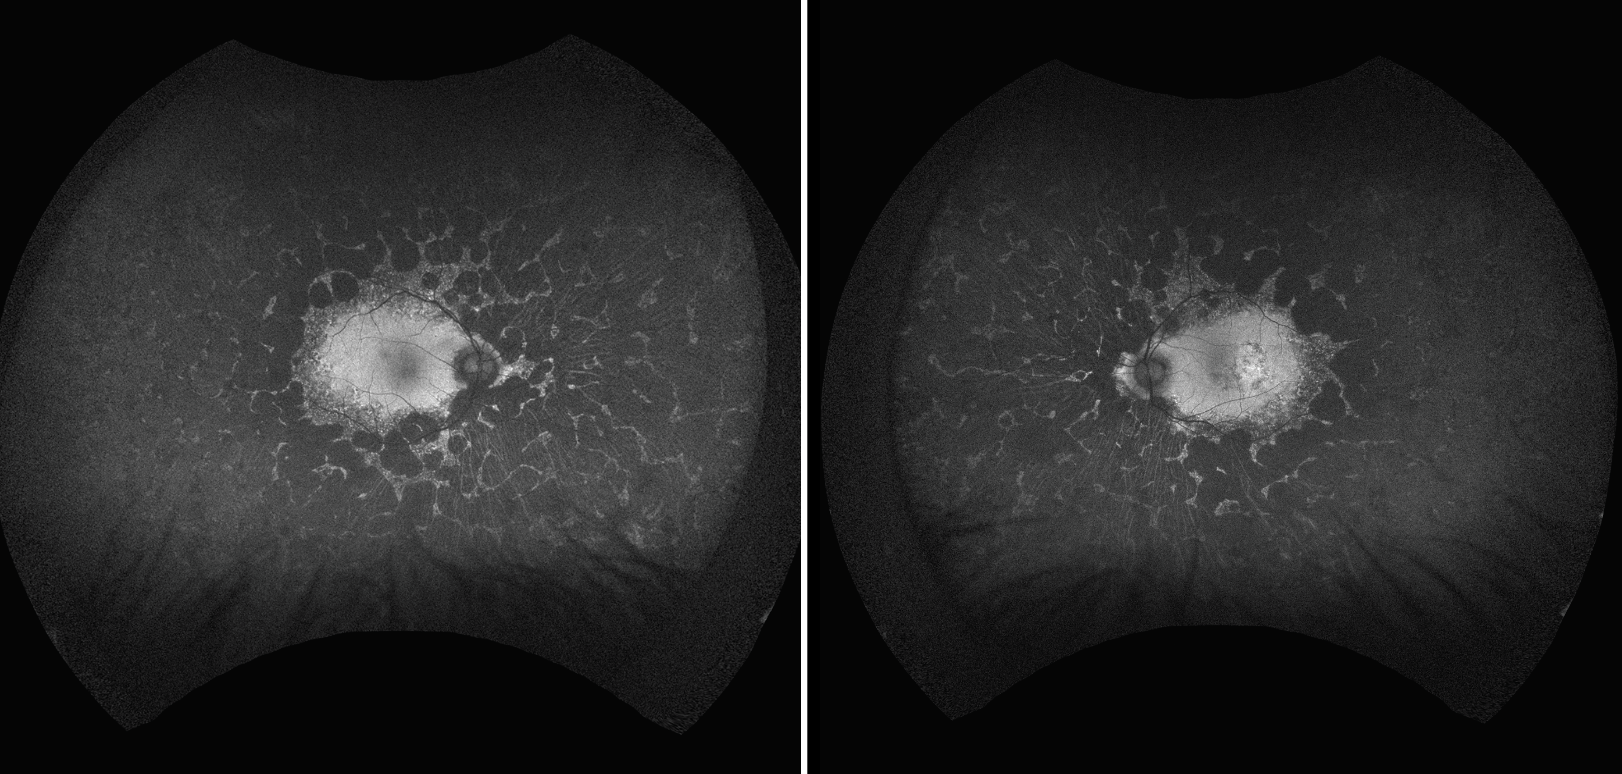

Fluorescein angiography revealed staining at the edges of the chorioretinal lesions as well as pinpoint areas along the arcades with relative sparing of the macula. The left eye exhibited a small area of staining in the temporal macula (Figure 4).

![]() |

| Figure 4. Late-phase ultra-widefield fluorescein angiography shows hyperfluorescence at the edge of the chorioretinal atrophy and along the arcades but sparing the macula. |